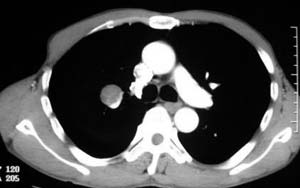

患者,男,58岁,煤矿职工,无症状,单位体检发现病变。

肺窗显示结节的后外边缘呈分叶状生长系生长过程受血管阻挡所致,出现较典型的“树凹”征,部分边缘见毛糙,不均匀强化,楼主未提供增强前后ct值,不好比较,倾向周围型ca。

右肺门上缘见类圆形节结影,密度尚均,边缘清楚,其内可见点状钙化影,周围支气管受压移位,病灶未见明显强化。考虑:1炎性假瘤  2 支持周围型肺ca (腺瘤)

右肺门上缘见类圆形节结影,密度尚均,边缘清楚,其内可见点状钙化影,周围支气管受压移位,病灶未见明显强化。考虑:良性病变——结核球可能性大,周围型肺癌待排。

病灶边缘光滑,似可见分叶征,未见明显毛刺。气管影轻度向右偏移。内可见点样钙化。邻近气道影通畅,考虑结核球可能。请楼主尽快公布结果

右肺门上缘见类圆形结节影,密度尚均,边缘清楚,其内可见点状钙化影,周围支气管受压移位,病灶未见明显强化。考虑:良性病变;首先考虑肺内错构瘤。次考虑肺内腺瘤。

病灶呈分叶型,边缘清晰,无毛刺,增强强化不明显,内见多发钙化,亦无卫星灶。多考虑良性病变。错构瘤可能性大。

病灶呈分叶型,边缘清晰,无毛刺,增强强化不明显,内见多发钙化,亦无卫星灶。多考虑良性病变。错构瘤可能性大或结核球。肺癌待排

动脉相上,右上肺动脉的尖段分支位于结节旁,结节对血管形成压迫而使到走行略改变,并没有很明确的包绕,也没有动脉期的供血,考虑还是偏向于良性可能大。当然最后的决定还是病检

病变边界清晰,对周围主要是外压性改变,未见血管包绕,边缘及中心见钙化,考虑良性病变,结核球可能